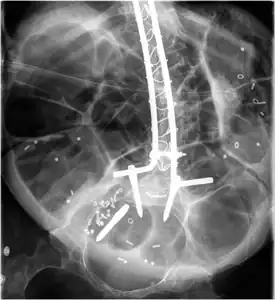

Radiograph of abdomen, of individual with Duchenne muscular dystrophy, spine stabilization is achived via rods and screws (one is displaced) and a Percutaneous endoscopic gastrostomy is visible